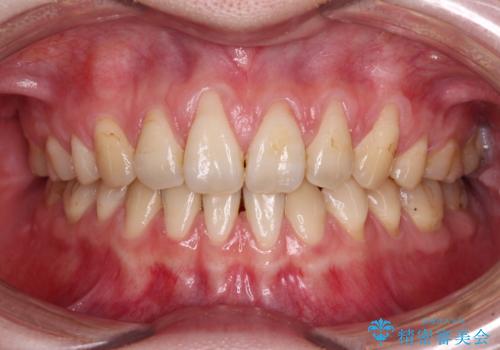

- 他院で矯正治療を終えた結果、上顎前歯の歯肉が退縮してしまい、根が見えていることが気になるとのことで来院された患者様です。

歯肉退縮に対して、上顎からの結合組織移植術(CTG)により、歯根の被覆を行うとともに、歯肉の厚みを増すことで将来の退縮リスクを抑制することとしました。

必要な被覆量が多かったため、満足のいく被覆を達成するには2度の手術が必要と思われましたが、生着がよく、術後の注意事項を徹底したことで、十分な被覆量を達成することができました。